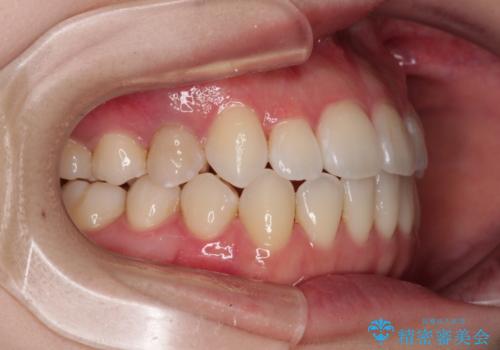

舌突出癖による開咬 舌のトレーニングを行いながら前歯の隙間を改善

ワイヤー矯正での開咬改善には時間がかかります。

舌の突出癖改善のトレーニングをしっかりと行っていただき、上下前歯が接触する咬み合わせを達成することができました。